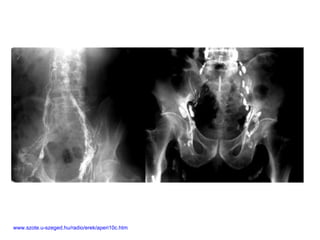

www.szote.u-szeged.hu/radio/erek/aperi10c.htm

Sistema Linfático Drenaro excesso de fluido intersticial para o sistema circulatório Transporte de nutrientes do sistema digestório para o circulatório Resposta imune O sistema linfático não realiza TROCAS – essa função é do sistema circulatório O movimento da linfa se faz através da compressão produzida pela contração vascular e muscular